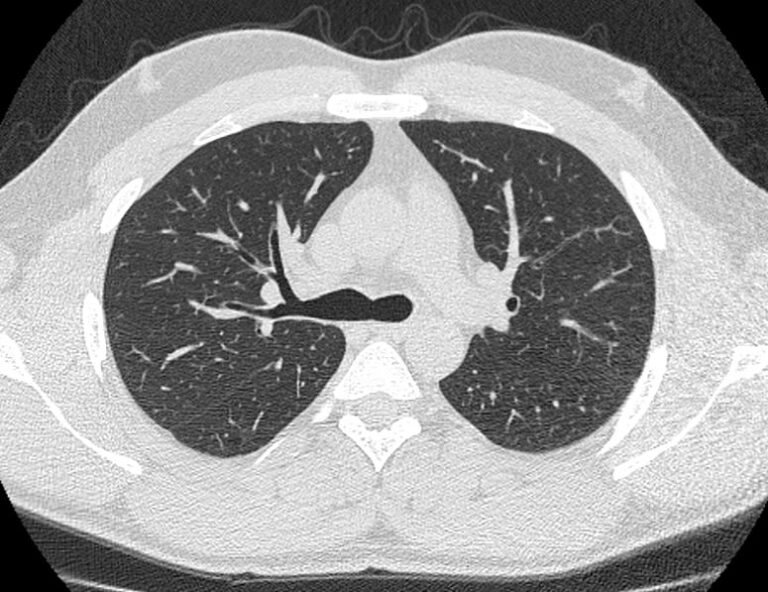

В нашей клинике КТ бронхов проводится на новейшем 128-срезовом мультиспиральном компьютерном томографе экспертного класса TOSHIBA AQUILION CXL. Аппарат оснащен увеличенным количеством сверхчувствительных детекторов, которые позволяют проводить тончайшие срезы анатомической области с толщиной от 0,5 мм за несколько секунд. Быстрое выполнение процедуры обеспечивает минимальный уровень рентгеновского облучения, при этом исследование выполняется без применения контрастирования.

На основе данных, полученных при сканировании, аппарат создает наглядную 3D модель бронхиального дерева с высочайшей точностью и достоверностью, которая позволяет просматривать интересующие анатомические структуры в разных плоскостях. Метод обладает высокой точностью и дает возможность исследовать мелкие бронхи и бронхиолы, которые из-за узкого просвета бывает невозможно осмотреть при помощи эндоскопической бронхоскопии (возможности метода ограничены размером зонда).